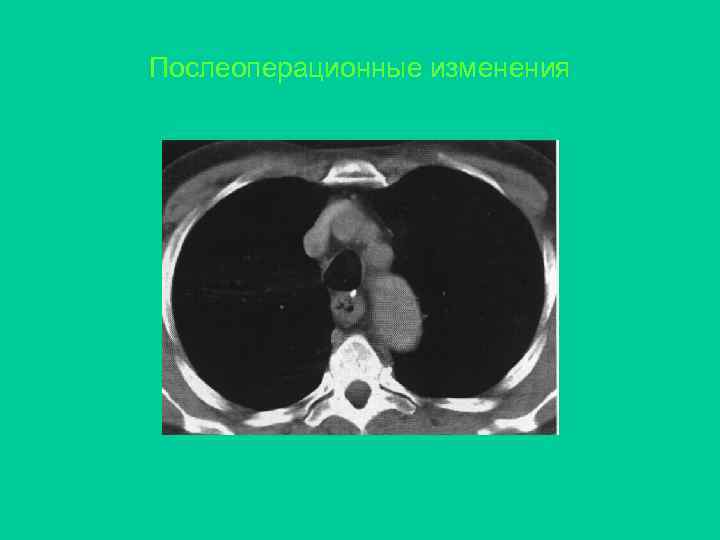

Послеоперационные изменения